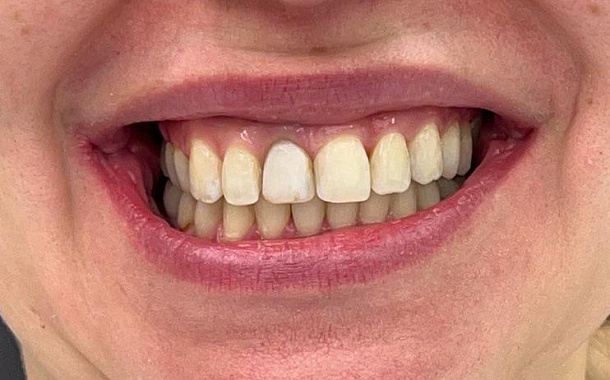

Полный прайс-листКейсы: до и после